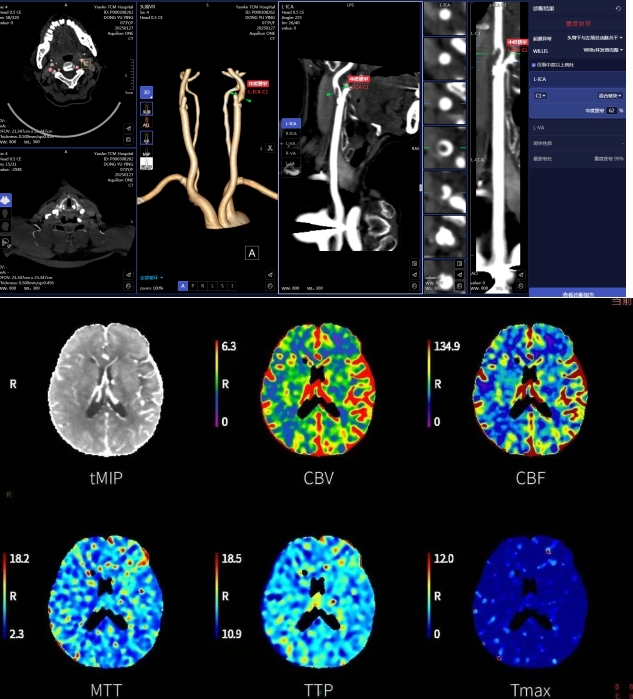

脑病科团队为患者查体,诊断为急性脑卒中。急查头颅核磁,结果显示左侧大脑半球多发急性期脑梗死,情况万分危急。此时,影像科的头颈CTA+颅脑CTP检查精准地揪出了隐藏在暗处的“罪魁祸首”——左侧颈内动脉起始处0.8cm的游离血栓,管腔重度狭窄,同时明确左侧额、顶、枕叶处于脑梗死前期分期(Ⅱ2期)。这一及时且精准的诊断,为后续的介入取栓治疗提供了依据,成功避免了再发脑梗死的后果,让患者重获新生。